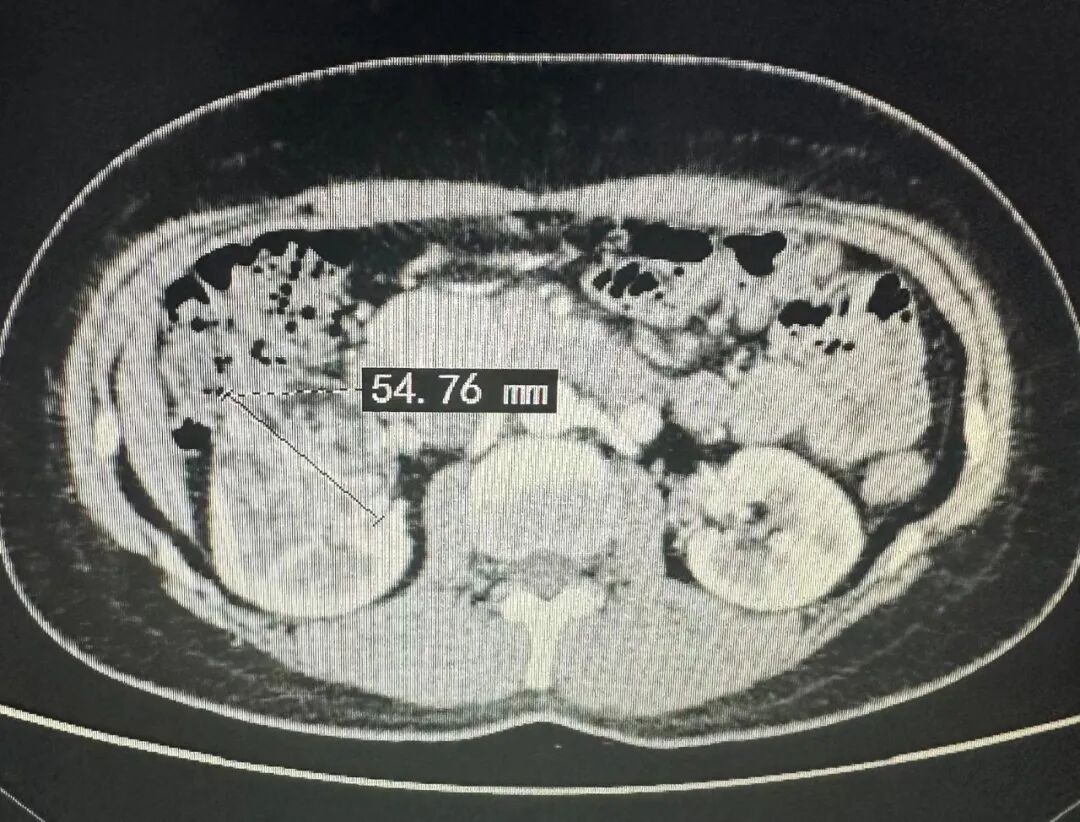

▲王女士体内长了6厘米大的左肾错构瘤

▲张女士左肾的肿瘤